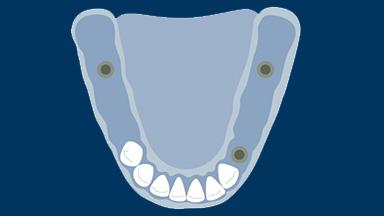

In combination with effective and hygienic conventional partial RDP design, strategic use of implants in these situations is gaining recognition as a simple, economical, but very effective means of enhancing the performance of partial RDPs and increasing patient satisfaction. This Learning Module will explore this use of implants in combination with conventional partial RDPs.

- describe indications for use of single unsplinted implants in combination with partial RDPs

- discuss the following supportive elements and superstructure options for single unsplinted implants: retentive stud attachments, functional single crowns